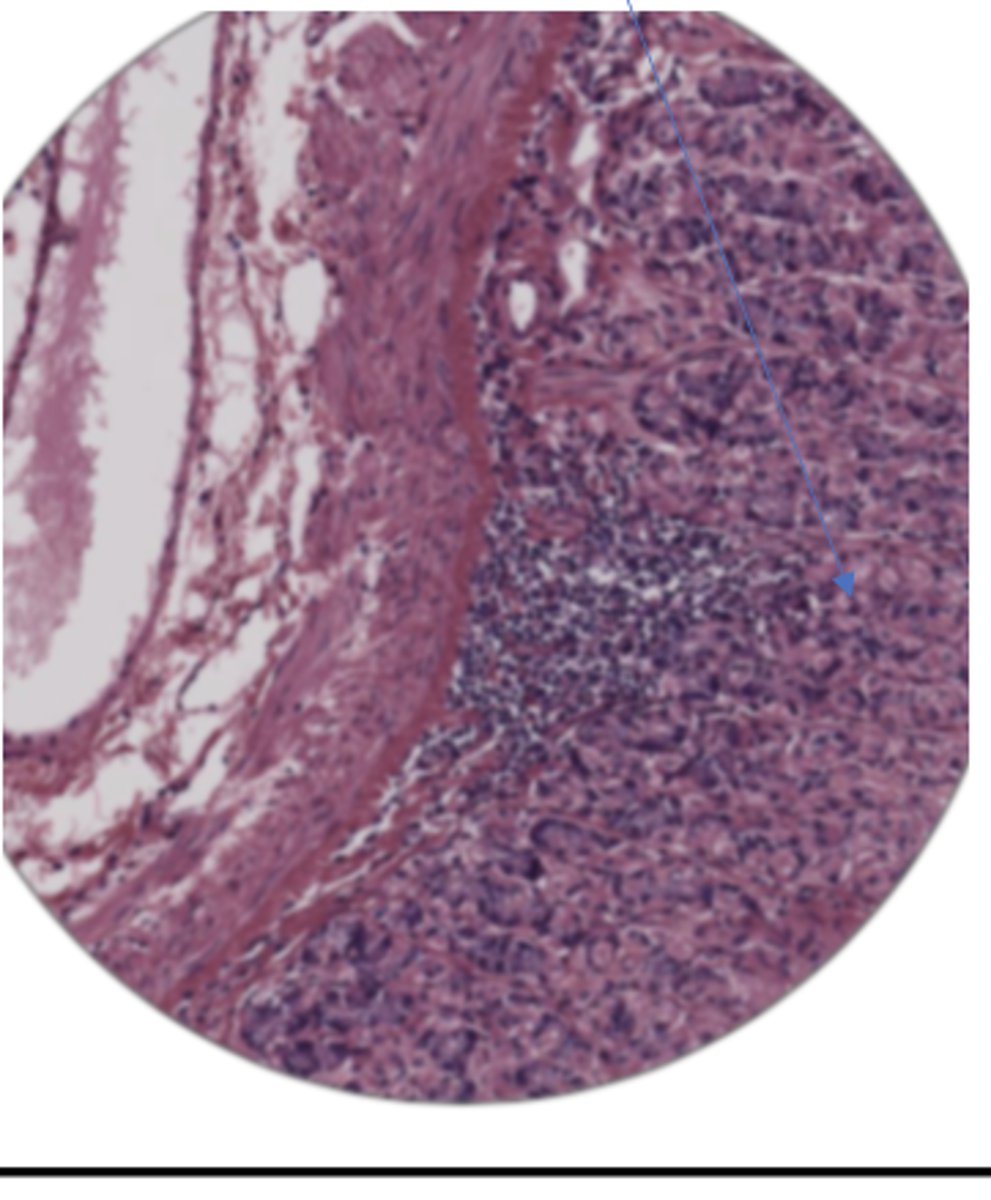

glomerulus

convoluted tubules

collecting duct